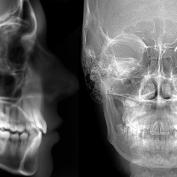

La cefalometria, definita anche di Ricketts, è un test radiologico noto che misura le proporzioni delle ossa del viso del paziente. Grazie a questo test possiamo creare uno studio cefalometrico completo del paziente e studiarne quindi le strutture ossee anche del cavo orale. La teleradiografia laterale del cranio è molto semplice da usare. Il paziente deve essere posizionato ad una certa distanza dalla macchina radiografica come contrassegnato dal braccio teleradiografico del dispositivo.

Il tracciamento cefalometrico o cefalometria, in ortodonzia viene eseguito mediante radiografia laterale del cranio o teleradiografia. È un punto di partenza per poter fare una corretta diagnosi e una previsione degli effetti della crescita, un metodo di valutazione della meccanica ortodontica da utilizzare e una base di lavoro per collegare la diagnosi con il trattamento. Dalla diagnosi corretta, un pian odi trattamento può essere elaborato e le opzioni di trattamento saranno diverse a seconda di tale diagnosi: ortopedia, ortodonzia o chirurgia ortognatica.

La cefalometria del rachitismo è una delle cefalometrie più utilizzate nel campo dell'ortodonzia perché può essere applicabile in ogni caso, può essere fatta una prognosi di trattamento e grazie a questa cefalometria c'è la possibilità di visualizzare la crescita. La cefalometria della teleradiografia laterale del cranio è indicata in alcune misure raggruppate in 6 campi